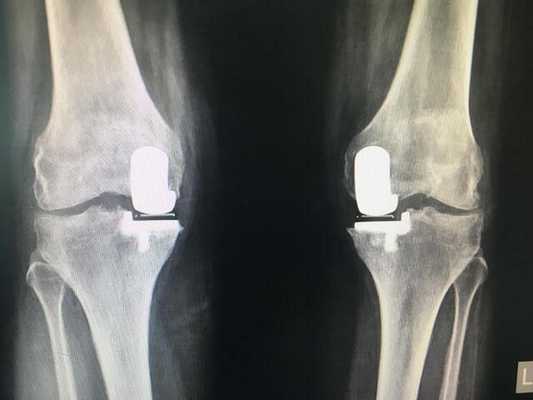

Одномыщелковая замена сустава на рентгене.

Сравнение двух типов операций.

С каждой последующей операции статистика успешности ниже. Импланты при этом становятся все более громоздкими.

Одномыщелковое протезирование подразумевает срок службы небиологического устройства максимум 7 лет. Тотальное замещение предусматривает время службы вживленного механизма от 15 лет. Ревизионное переносится сложнее, а риск инфекции и других негативных явлений почти в 2 раза выше, чем после первичной операции.